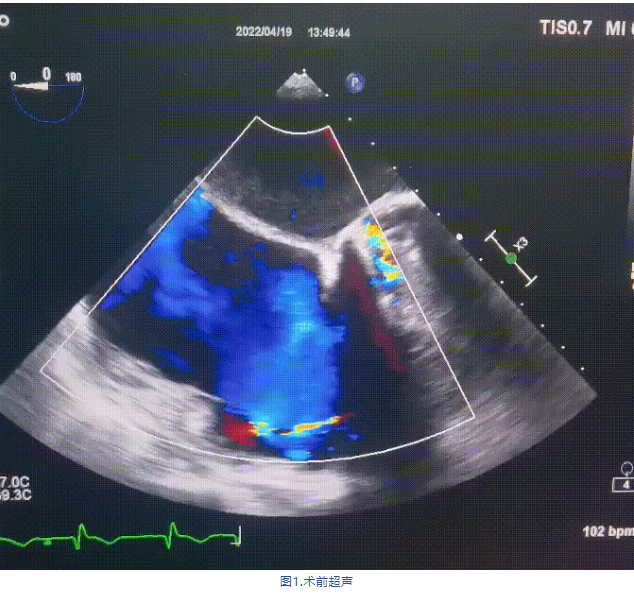

術(shù)前超聲提示:

1.右心、左房明顯增大;

2.二尖瓣人工機械瓣功能正常,無瓣周漏;

3.三尖瓣環(huán)巨大擴張,收縮期瓣葉對合不攏,收縮期三尖瓣房側(cè)見大量反流信號,反流面積15-20cm²,TRVmax:240cm/s,跨瓣壓差:23 mmHg。